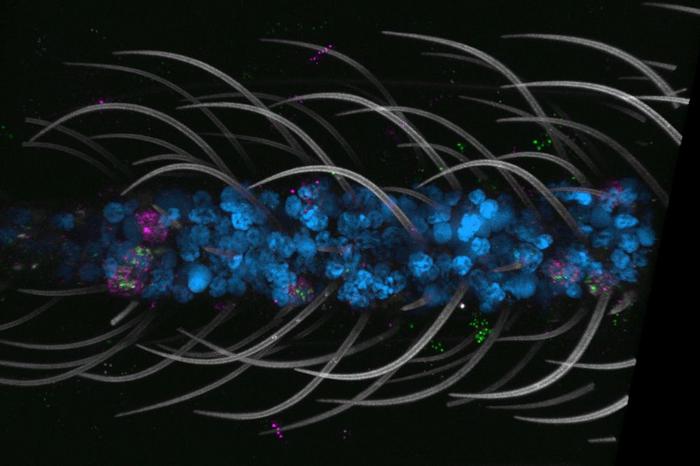

Study Finds Weightlifting Superior to Running for Blood Sugar Control

A groundbreaking study from the Fralin Biomedical Research Institute at Virginia Tech offers compelling evidence that resistance training may surpass…